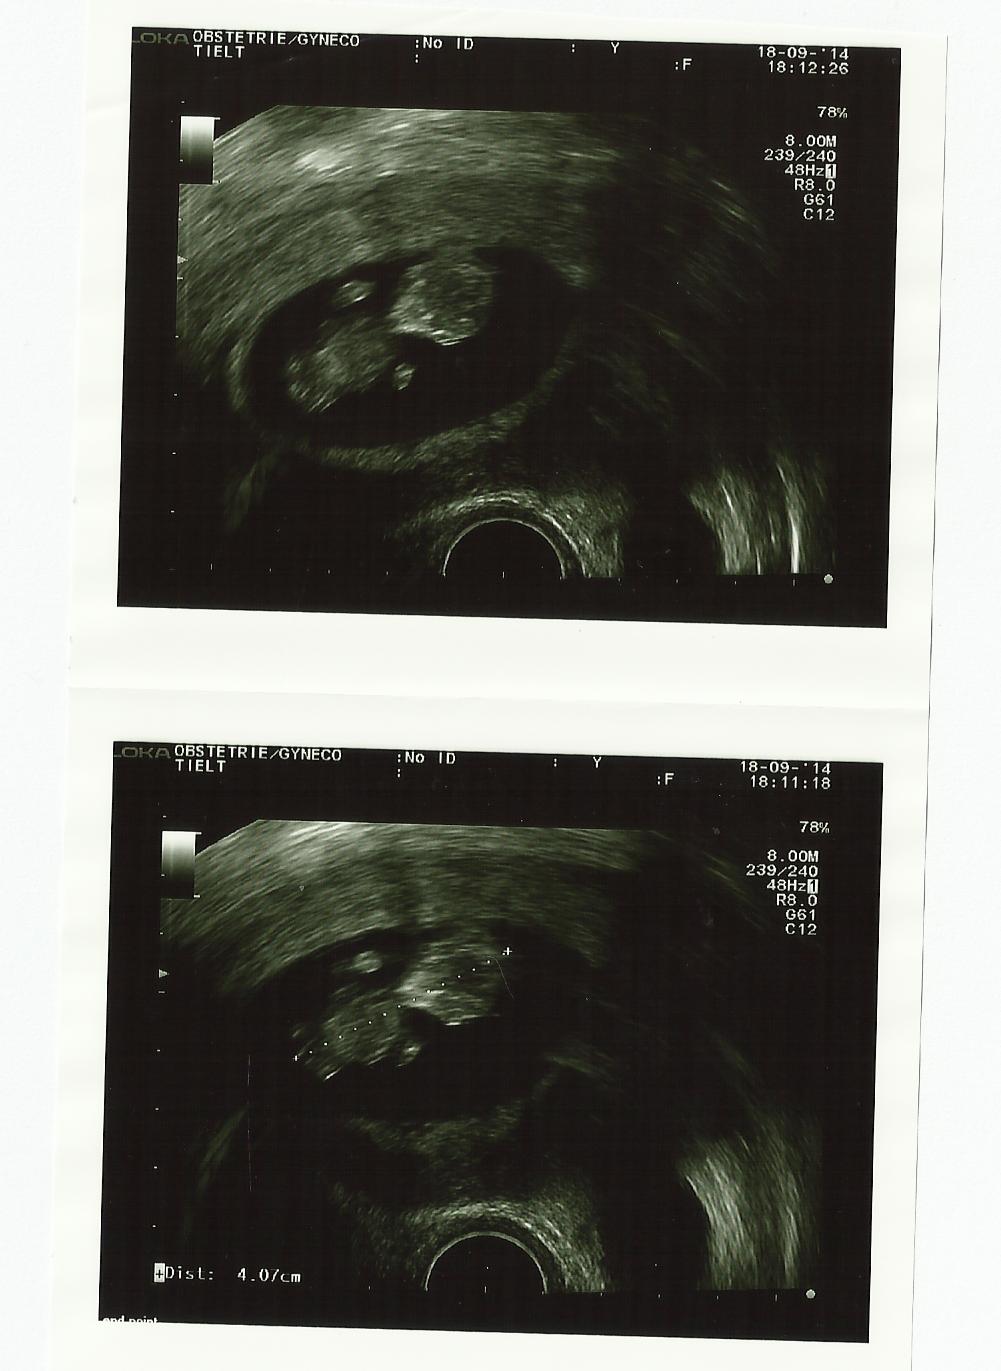

Op 10 weken en 5 dagen ben je 4 cm groot. Volgens de gynaecologe is dit groot voor jouw leeftijd! Jouw hartje klopt goed en jouw armpjes en beentjes beginnen te groeien.